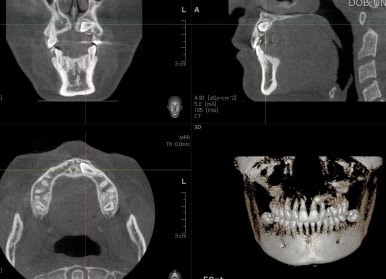

부산매복치아교정 키다리아저씨치과에서 촬영한 3D CT에서는 이처럼 입체를 연속적인 단면으로 재구성하여 정확한 위치를 파악할 수 있게 해줍니다.

매복치의 위치는 가로로 누워있고, 머리는 앞쪽, 뿌리는 뒤쪽을 향하며 다른 치아들보다 입천장쪽에 있습니다.

부산매복치아교정 키다리아저씨치과에서 촬영한 3D CT를 입체사진으로 재구성해보면 훨씬 직관적으로 눈에 띄게 위치를 판단할 수 있게 해줍니다.

위치를 정확하게 파악하는 것이 중요한데 결국은 잇몸을 째고 정확한 치아 머리를 향하여 들어가서 장치를 부착해야 되기 때문이죠.